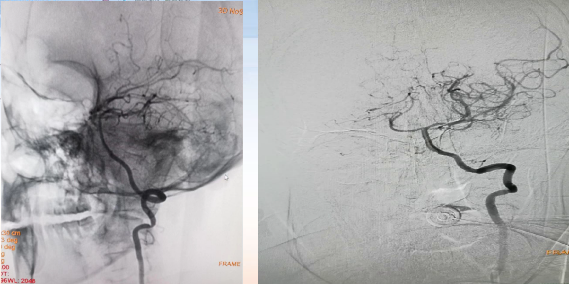

手术评估

病历夹什么径技·第152期|串联营病历夹:川陕大营_https://www.jmylbn.com_新闻资讯_第90张

病历夹什么径技·第152期|串联营病历夹:川陕大营_https://www.jmylbn.com_新闻资讯_第91张

病历夹什么径技·第152期|串联营病历夹:川陕大营_https://www.jmylbn.com_新闻资讯_第92张

术后情况

• 术后24小时,左侧肢体肌力4级,凝视消失,NIHSS 6